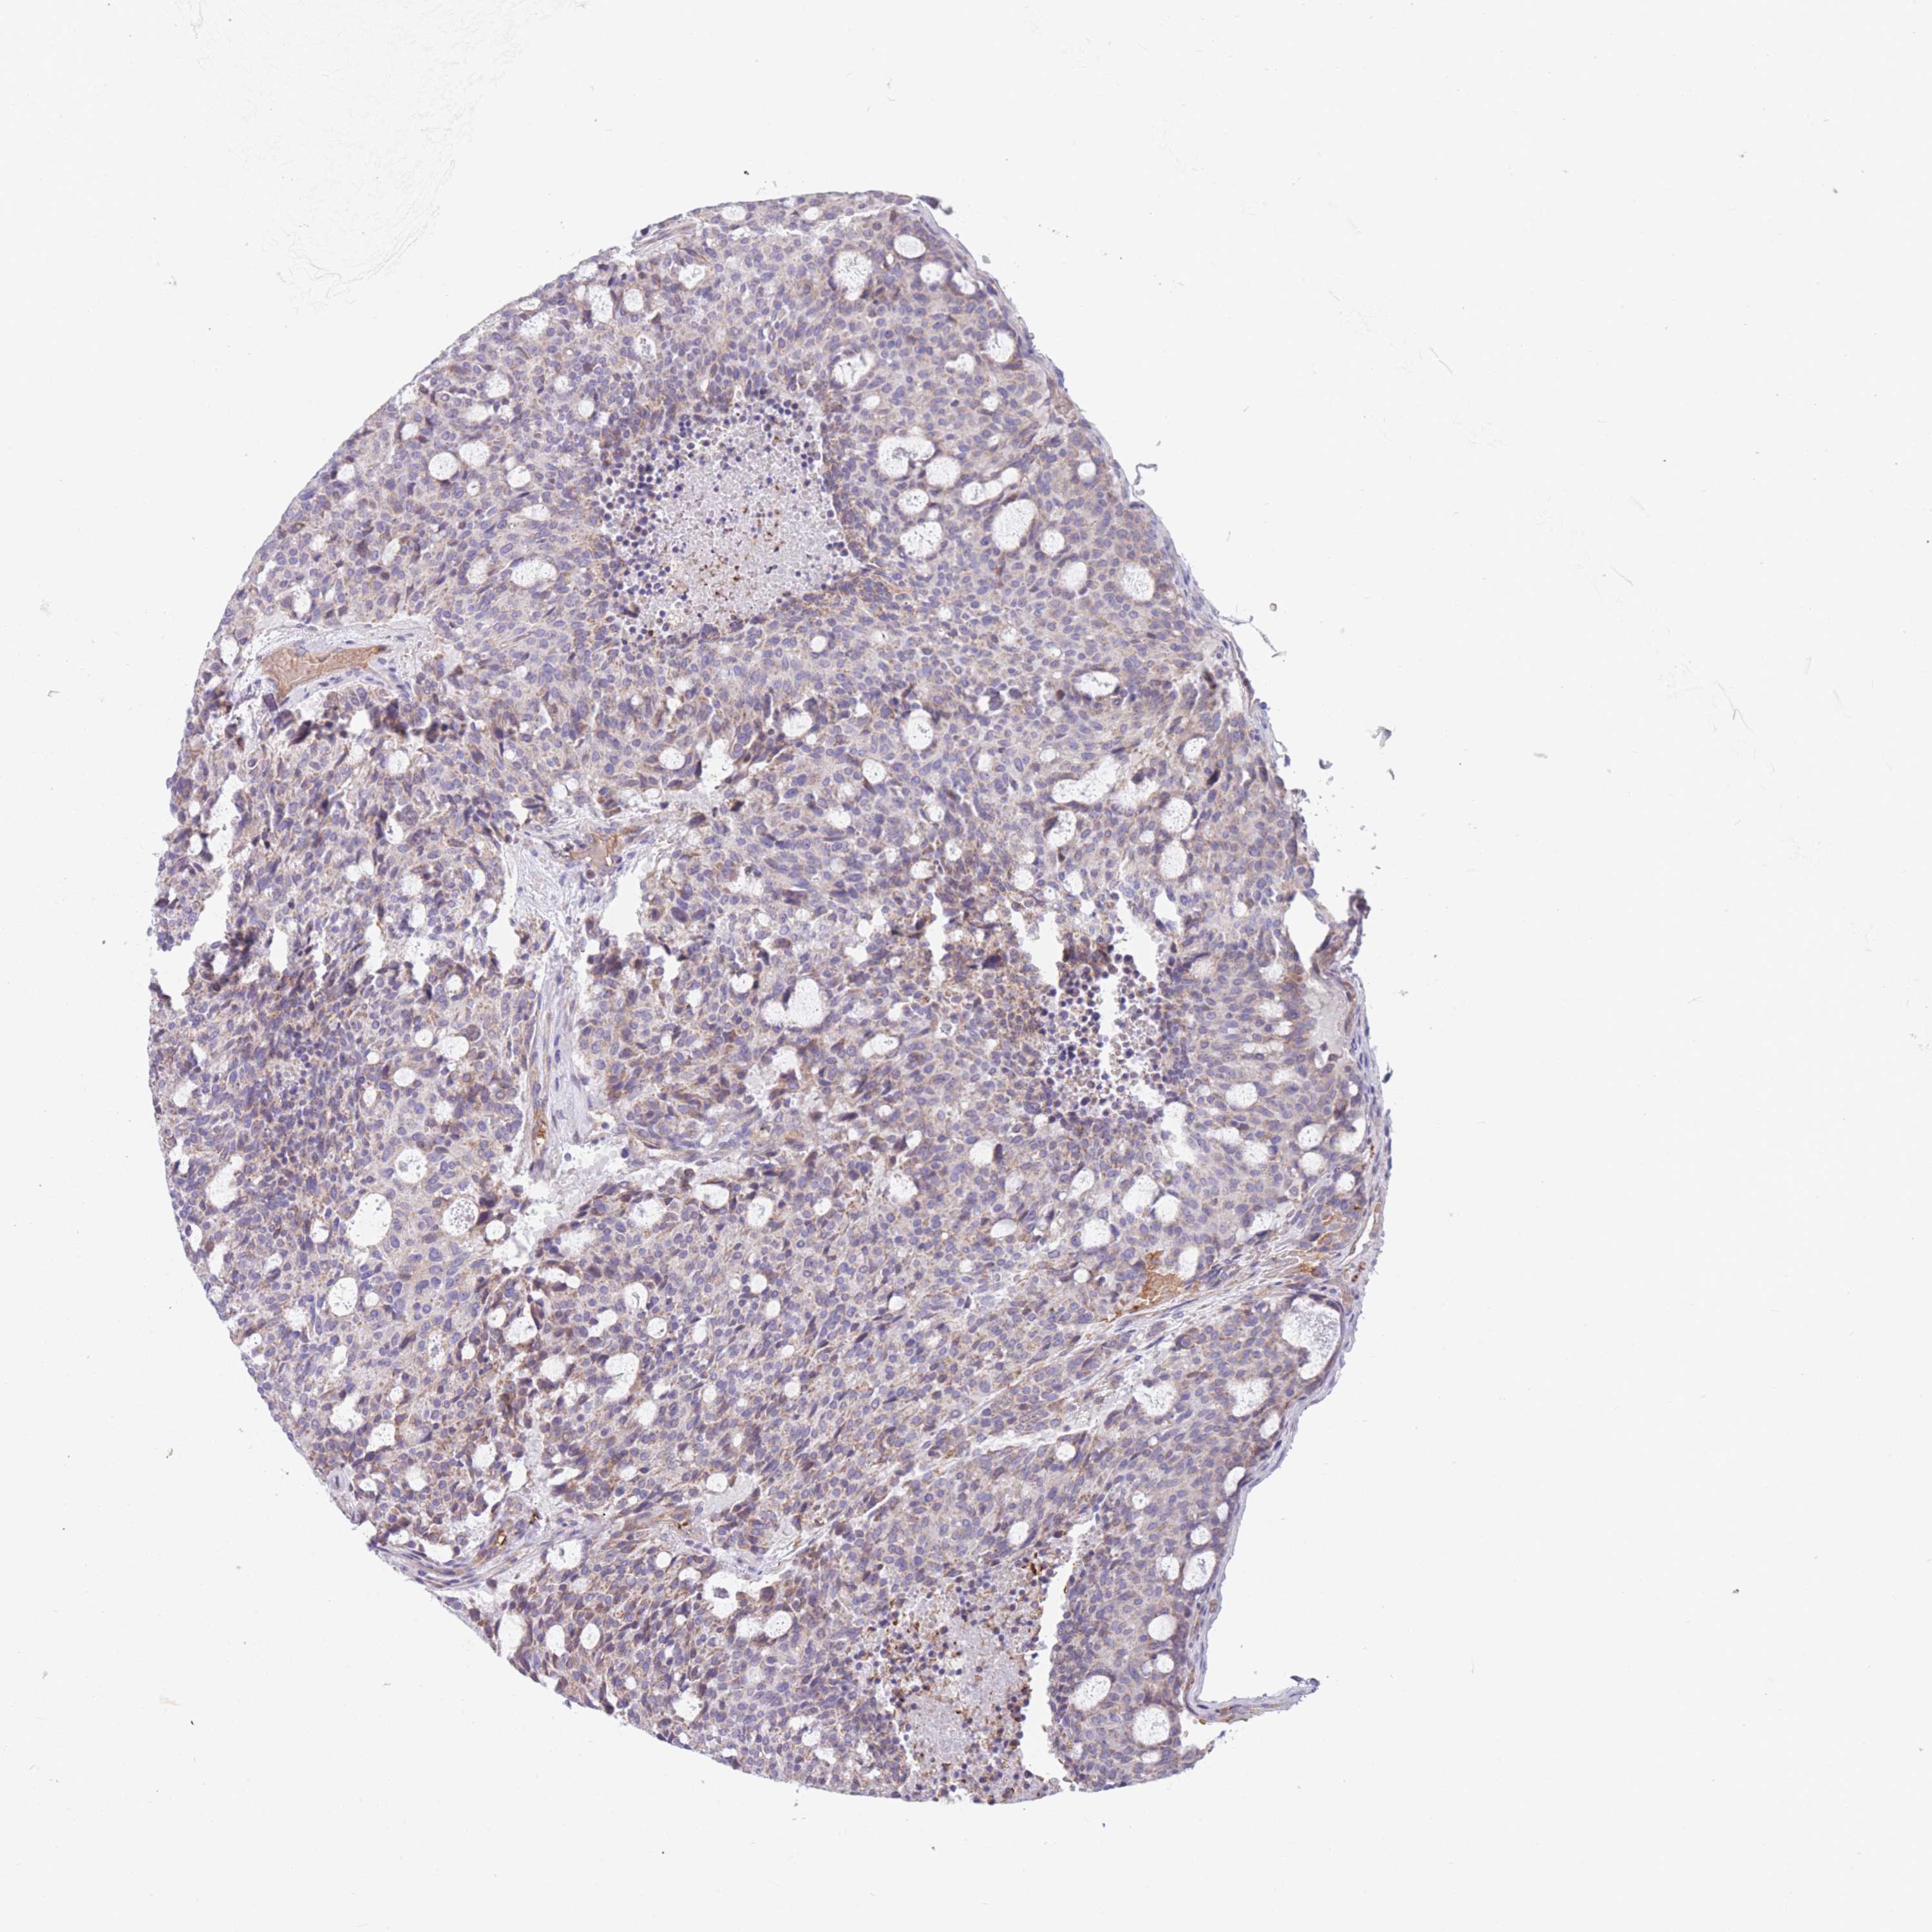

Neuroendocrine tumors

Human pathology

Carcinoid